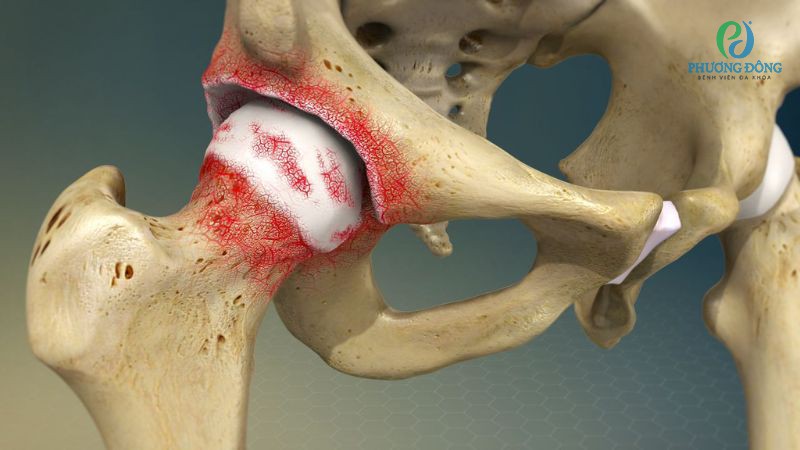

Trật khớp hông

Trật khớp hông, còn gọi trật khớp háng, xác định khi chỏm xương đùi bị lệch khỏi ổ cối của khớp háng. Người bệnh dễ dàng nhận biết thông qua các cơn đau nhức dữ dội, vùng hông biến dạng, khớp háng khó cử động, cơ co thắt hoặc chân ngắn chân dài.

Dạng chấn thương này cần được can thiệp y tế sớm, tiếp nhận chỉ định phù hợp. Trường hợp kéo dài có thể kéo theo loạt biến chứng nguy hiểm như chèn ép thần kinh tọa, thiếu máu nuôi chỏm xương đùi.